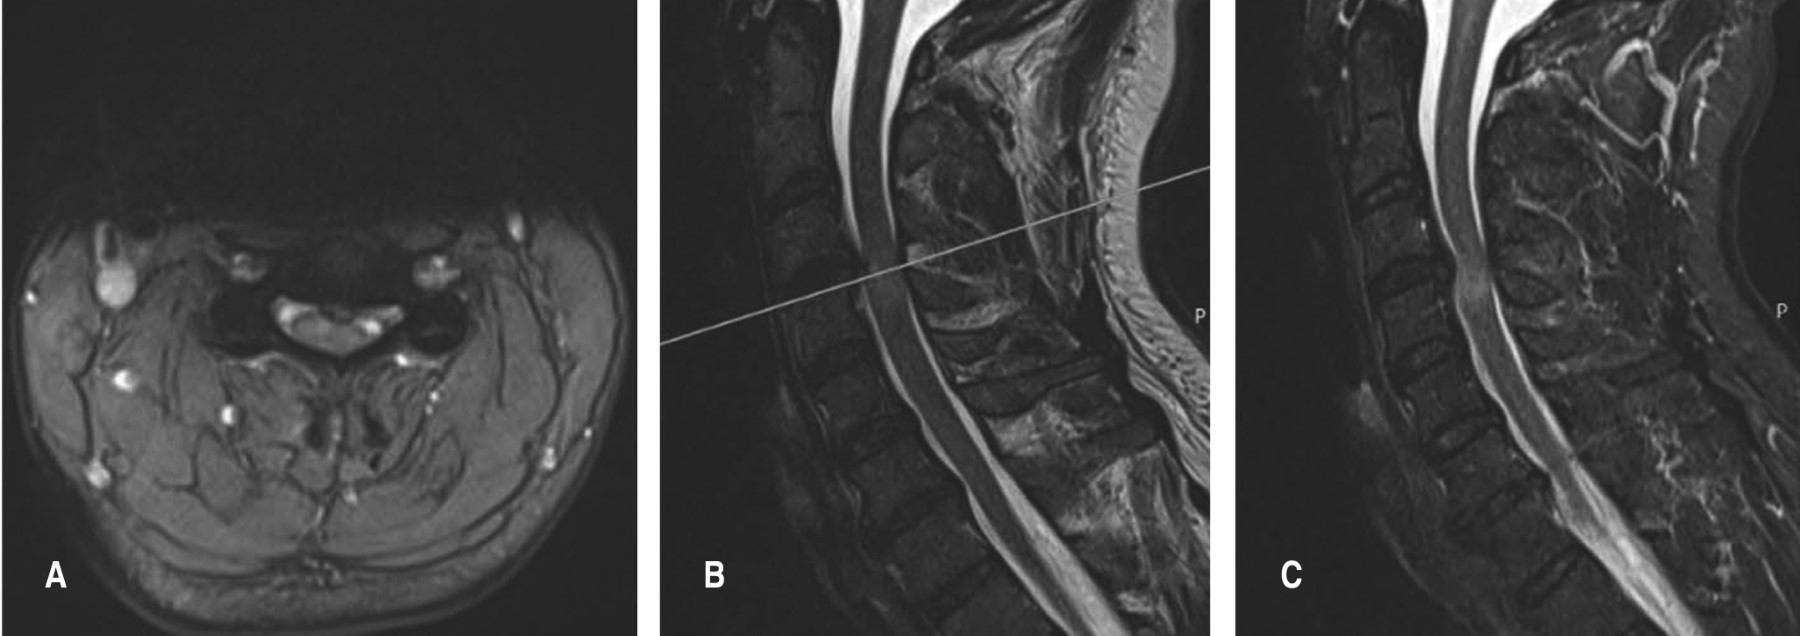

La hernia cervical traumática sin lesión ósea o articular asociada a mielopatía es una patología rara. Los casos reportados en la literatura tuvieron un diagnóstico tardío, secundario a hallazgos clínicos y radiológicos que pueden pasar desapercibidos. Habitualmente, el primer contacto con el paciente no lo realiza un cirujano especialista en columna. Se presenta el caso de un paciente masculino con traumatismo facial, que desarrolló una mielopatía cervical dos semanas después por hernia cervical traumática en C3-C4 sin lesión ósea, que no fue diagnosticada precozmente, posteriormente el paciente presentó alteración neurológica y requirió tratamiento quirúrgico para su descompresión y artrodesis anterior, con buenos resultados a los seis meses de seguimiento.

Figura 2